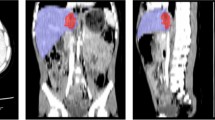

Our pipeline includes 4 parts: (1) automated splenic localization, (2) Faster R-CNN-based detection of pseudoaneurysms (PSA) and active bleeds (AB), (3) nnU-Net segmentation and quantification of splenic parenchymal disruption (SPD), and (4) a directed graph that infers AAST grades from detection and segmentation results. Training and validation is performed on a dataset of adult patients (age ≥ 18) with voxelwise labeling, consensus AAST grading, and hemorrhage-related outcome data (n = 174).

AAST classification agreement (weighted κ) between automated and consensus AAST grades was substantial (0.79). High-grade (IV and V) injuries were predicted with accuracy, positive predictive value, and negative predictive value of 92%, 95%, and 89%. The area under the curve for predicting hemorrhage control intervention was comparable between expert consensus and automated AAST grading (0.83 vs 0.88). The mean combined inference time for the pipeline was 96.9 s.